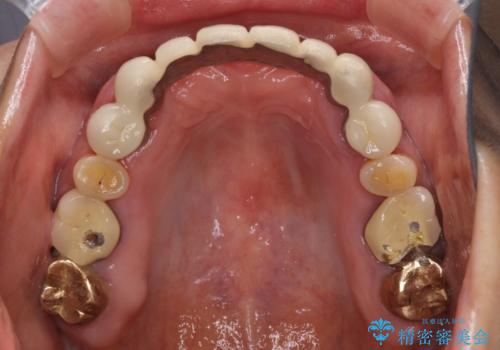

- 全顎的な歯肉からの出血と前歯の形態を気にして来院された患者様です。

診査の結果、上顎奥歯を中心に深い歯周ポケットが認められたため、歯周ポケット除去を目的とした歯周外科処置を行うこととしました。

また、前歯のブリッジへの咬合力の負担が大きく、土台となっている歯が揺れてしまっていたため、インプラント埋入により奥歯への負担を軽減することとしました。